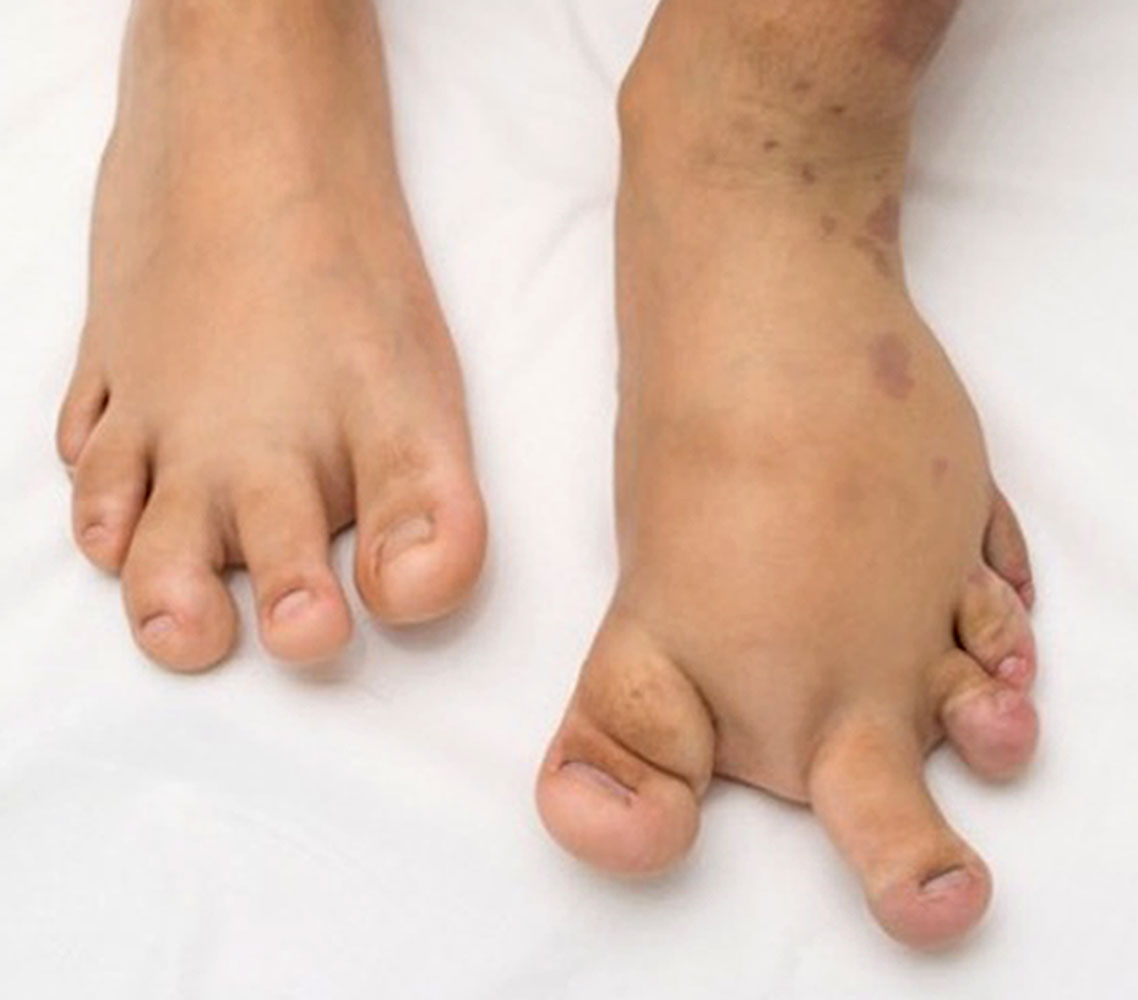

Der regionale Überwuchs mit vorherrschender Weichteilkomponente ist bereits bei Geburt vorhanden und betrifft am häufigsten die Füße. Der „CLOVE-Fuß“ hat ein charakteristisches Aussehen: Verbreiterung insbesondere des Vorfußes („ballonierte Hyperplasie“), fibroadipöse Weichteilvermehrung, Sandalenlücke.

Einzelne oder mehrere Zehen können vom Überwuchs betroffen sein. Im Gegensatz zum Proteus-Syndrom bleibt trotz des oftmals massiven Überwuchses einzelner Knochen deren Form weitgehend erhalten. Desweiteren finden sich Lipomatosen, mitunter großflächig, besonders am Rumpf. Häufig weisen Patienten mit CLOVES-Syndrom auch Lipoatrophien auf, diese betreffen meist die Arme. Der zugrundeliegende Mechanismus der Fettgewebsdysregulation ist bisher nicht verstanden.